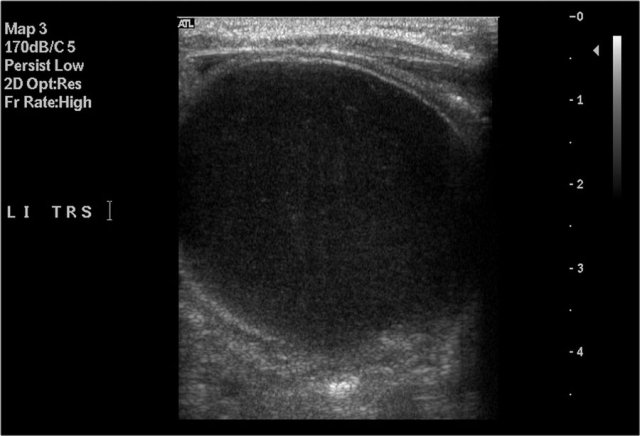

The image is of a one-month-old boy with a MCKD on prenatal ultrasound.

Some tissue and several large cysts are seen.

On Tc-99-DMSA scintigraphy no uptake was seen on the left side.

This is compatible with a MCKD.